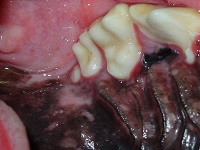

d) Unless the teeth cause a traumatic malocclusion or have the potential to increase the risk for periodontal disease they do not need to be extracted. In the following 2 examples the supernumerary molar tooth does not need to be extracted whereas the supernumerary canines do.

Hyperdontia Supernumerary Tooth Dec 2008-02 Hyperdontia Supernumerary Tooth Dec 2008-03